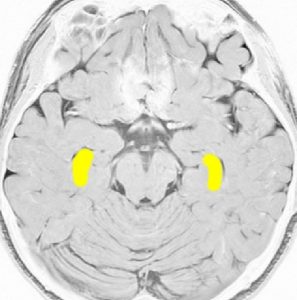

海馬

両側の側頭葉の内側にあり,学習,記憶,空間認識(spartial awareness。物体のある場所・大きさ・形・速さ・向き・物体同士の位置関係などを素早く正確に認知する能力)を司ります

記憶に関しては左側の海馬に優位性が大きいです